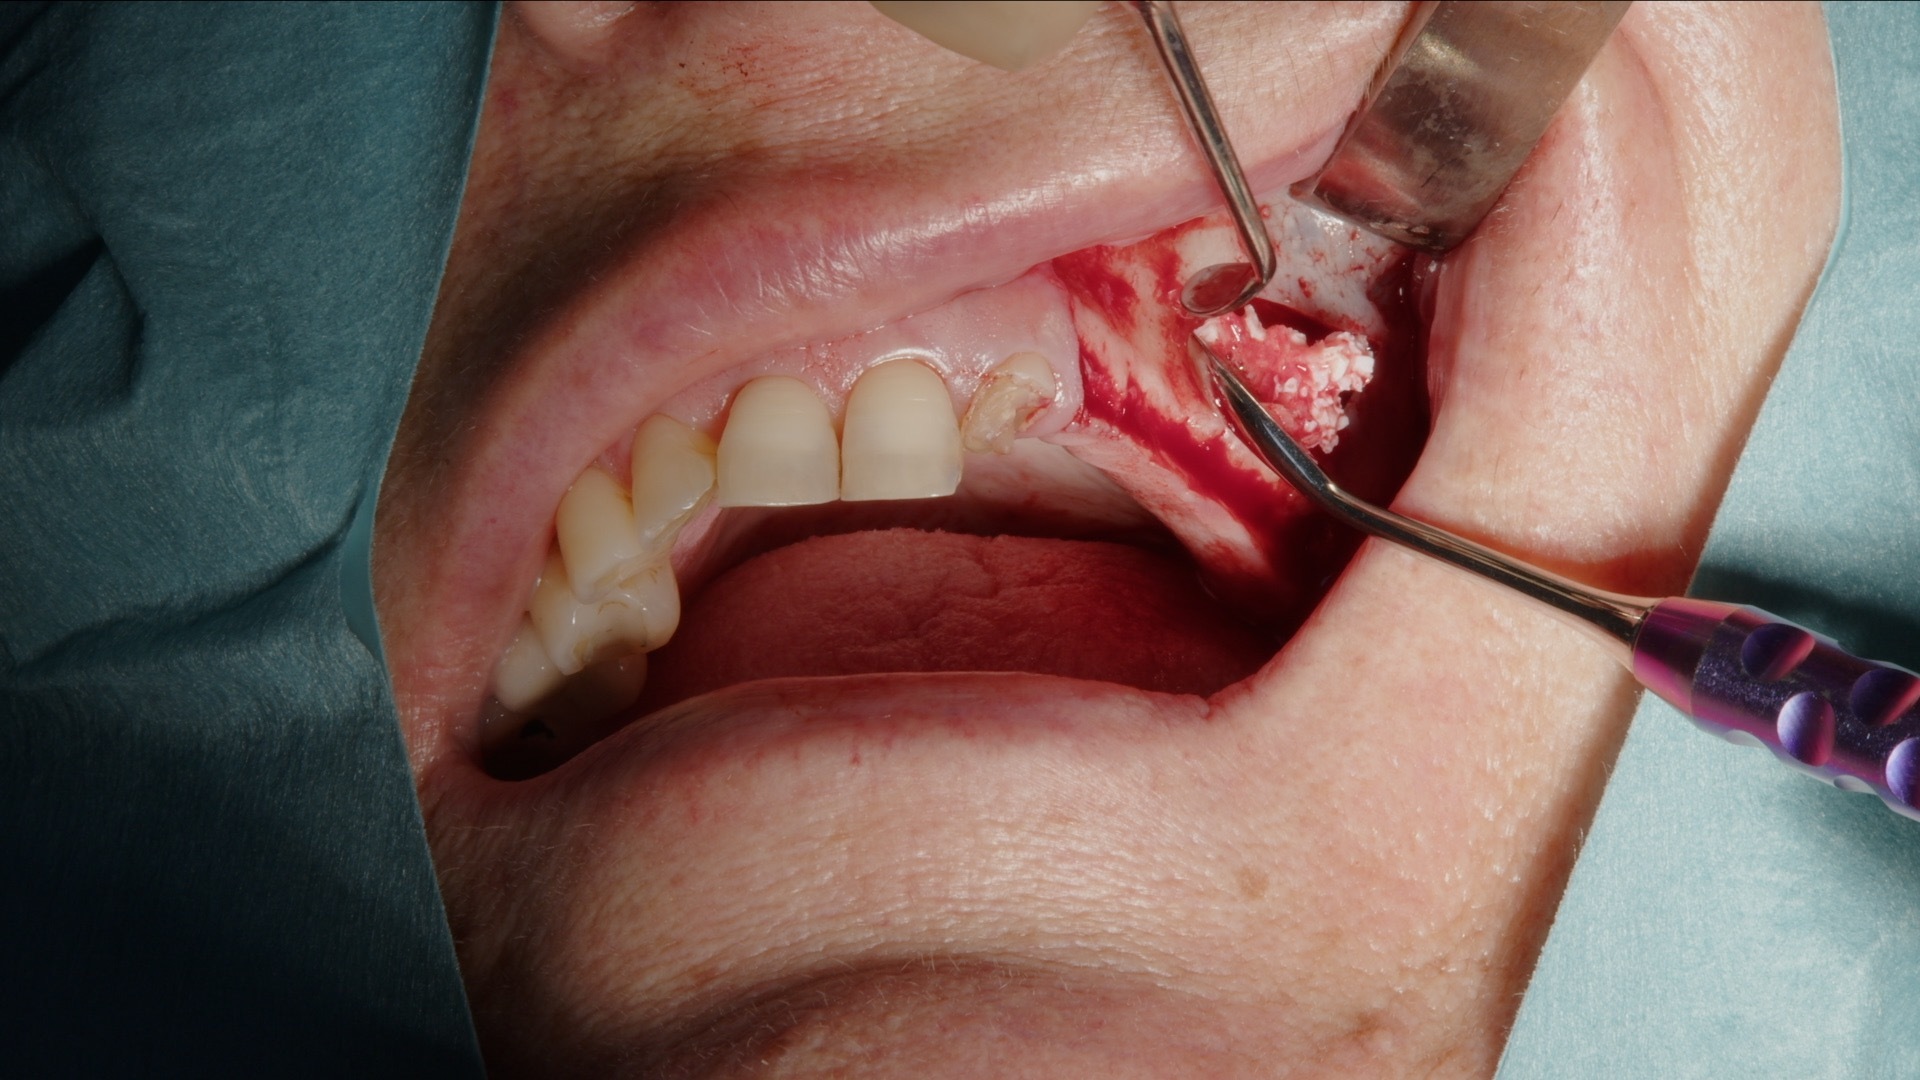

5. Utfylling med blanding av Geistlich Bio-Oss og autologt ben.

Autologt ben høstes med Safescraper direkte fra operasjonsområdet. Metoden er minimalt invasiv og gir vitalt benmateriale med høy biologisk potensial. Det autologe benet blandes deretter med Geistlich Bio-Oss for å skape en stabil graftmasse med både osteokonduktive og osteoinduktive egenskaper.

Den ferdige blandingen plasseres systematisk i det etablerte sinusrommet til ønsket volum er oppnådd. Kombinasjonen gir god vaskularisering, langsiktig volumstabilitet og forutsigbar benregenerasjon.